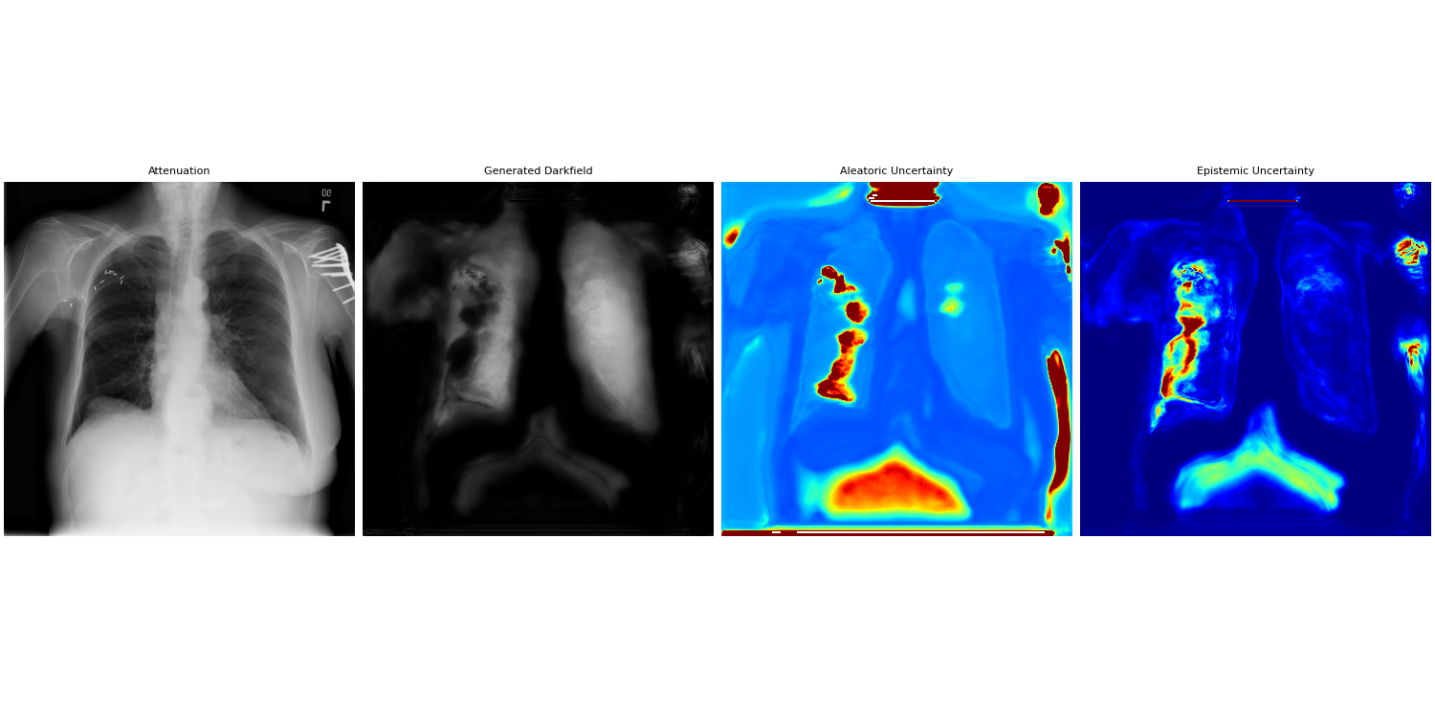

Figure 5 shows the results for the out-of-distribution data from the NIH Chest X-ray dataset. We present the attenuation images, the generated dark-field images, and the corresponding aleatoric and epistemic uncertainty maps for two patients. For the first patient, the model generates realistic dark-field images, with both uncertainty types remaining at similar and relatively low levels. The attenuation image of the second patient contains cables, a pacemaker, and lead markers, features that are not or only rarely present in the training data. Despite these out-of-distribution elements, the model is able to generate a visually plausible dark-field image. The corresponding uncertainty estimates reflect this deviation from the training domain. For the third patient, however, we observe a failure case: the left lung exhibits artifacts in the generated dark-field image. This issue is also reflected in increased aleatoric and epistemic uncertainty. In addition, the model shows pronounced uncertainty in the upper abdominal region.

Attenuation Gen. dark-field Aleatoric Epistemic

Patient 1

Patient 2

Patient 3

The uncertainty analysis provides insight into the model’s behavior. As artifacts such as rib shadows diminish across the refinement stages, the aleatoric uncertainty also decreases, suggesting that it serves as a reliable indicator of reconstruction quality. Higher uncertainty values are observed in the lung regions for all three stages. This is expected, as lung tissue exhibits noisy and heterogeneous structures, making the prediction more ambiguous. The model thus appears to meaningfully capture both data-driven and structural uncertainty.

The out-of-domain evaluation further supports the robustness of the approach. Despite the presence of unseen image features such as cables, pacemakers, and lead markers, the model produces high-fidelity dark-field images, while also expressing appropriate uncertainty levels. This behavior reflects well-calibrated uncertainty estimation and provides confidence that the model can flag unreliable predictions when confronted with unfamiliar anatomical or device structures. This is further illustrated by the third patient, where the overall image contrast is notably higher than in other cases, likely contributing to the model’s failure and the corresponding increase in both aleatoric and epistemic uncertainty.

Although the aleatoric and epistemic uncertainty maps show similar spatial patterns, they reflect different aspects of model confidence. High aleatoric uncertainty marks regions with ambiguous signals, while elevated epistemic uncertainty highlights areas where the model may not generalize well. Together, they offer a more complete view of model reliability and data quality.